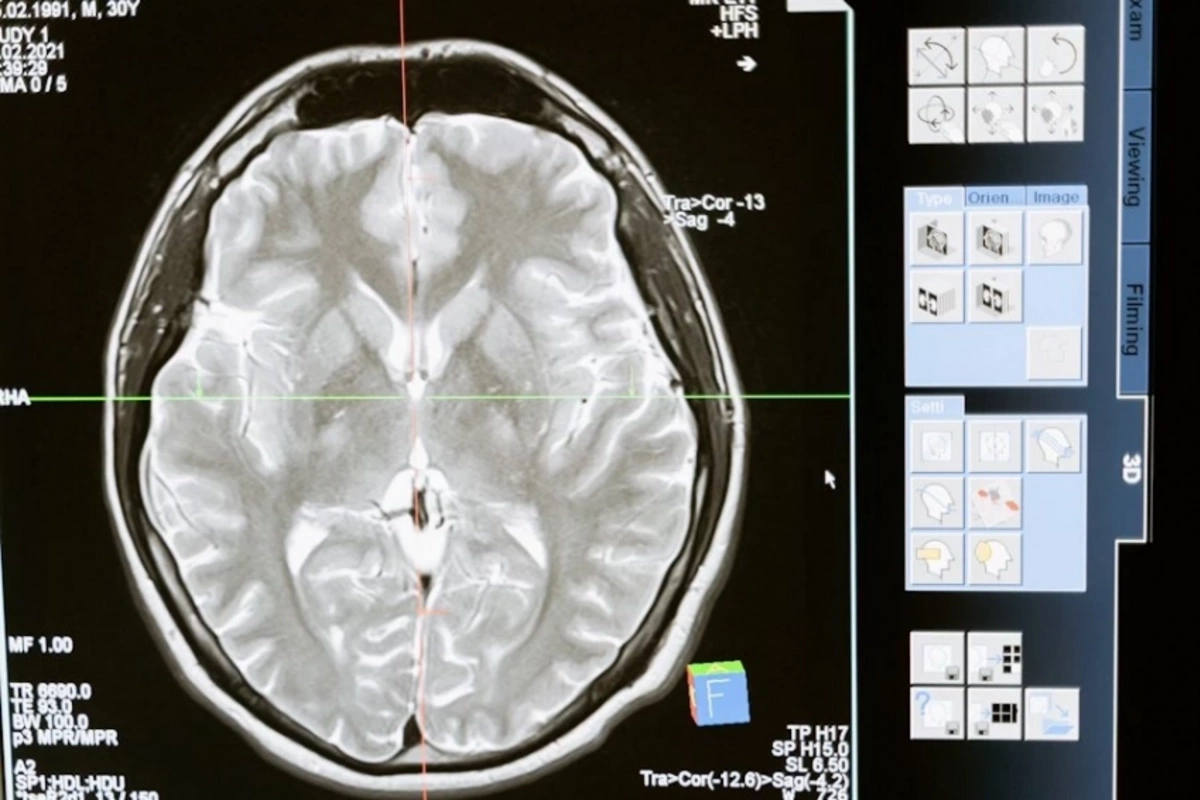

Ученые США предложили новый способ доставки противоопухолевых лекарств против глиобластомы - одного из самых агрессивных видов рака мозга. Метод основан на назальном введении специальных наноструктур, способных активировать иммунный ответ в опухоли.

Глиобластома зачастую плохо реагирует на терапию, в том числе из-за так называемой "холодной" иммунной среды: присутствие опухоли практически не активизирует естественную защиту организма. Усилить иммунитет может активация особого внутриклеточного пути STING. Однако препараты, воздействующие на него, быстро разрушаются и требуют прямого введения в опухоль, что делает лечение крайне сложным и инвазивным.